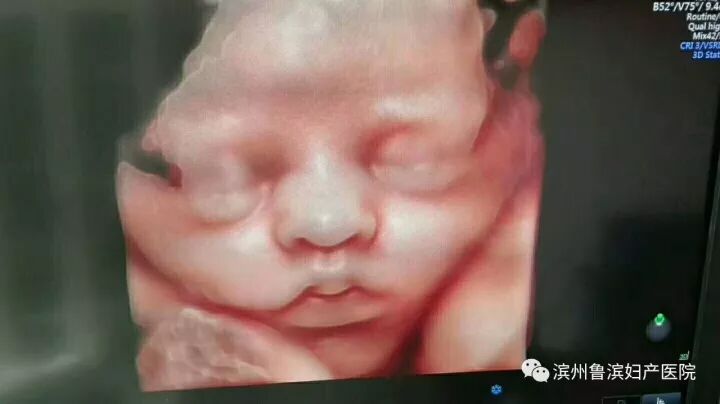

我院E10下熟睡的胎宝宝

相较普通四维彩超,E10的高清画质堪比IMAX电影大片!您可以亲眼目睹他们的一举一动和乖巧秀容,包括:皱眉、微笑、打哈欠、吸吮和吞咽、小腿交叉盘坐等,提前享受将为人母的喜悦。